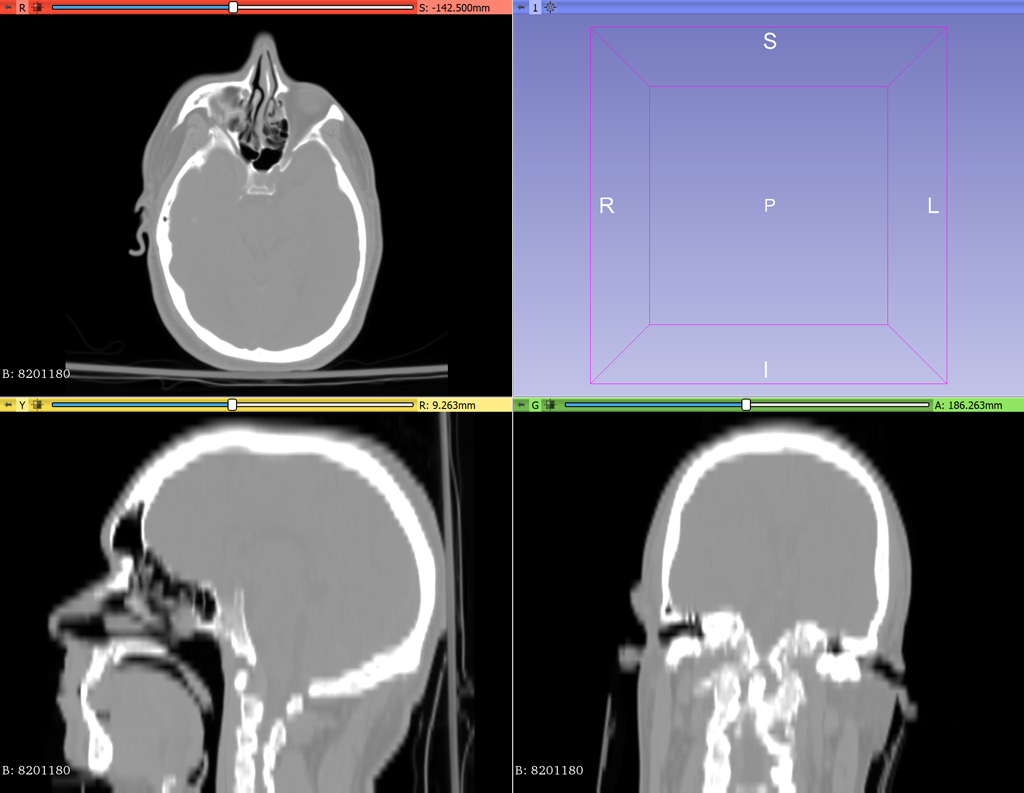

The data on the dics was a series of DICOM files, a format used for medical imaging. I managed to convert the files into a format that could be uploaded to a cloud-based segmentation system. This system allowed me to isolate different anatomical structures, effectively separating the face, skull, and brain from the rest of the scanned data.